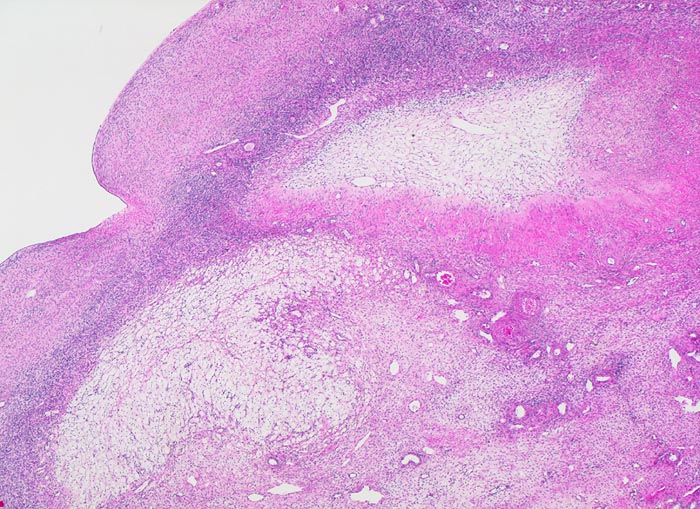

atretischer Follikel

Rechts oben im Bild ein atretischer Follikel: Die zentrale Zone wird durch lockeres Bindegewebe ersetzt. Die Zona pellucida (Basalmembran) ist kollabiert und ist gekräuselt und umfasst das lockere Zentrum. Degenerierendes Corpus luteum menstruationis links unten im Bild bestehend aus hellen Granulosaluteinzellen mit lipidreichem Zytoplasma und pyknotischen Kernen.

Im Verlauf des Lebens geht ein Grossteil der Primordialfollikel zu Grunde ohne eine Narbe zu hinterlassen. Eine Minderheit entwickelt sich weiter und können in jedem Stadium der Entwicklung atresieren. Nach der Atresie eines grossen Follikels kann sich eine grosse kollagene Narbe bilden, ein Corpus fibrosum, welches wie ein Corpus albicans geformt ist.